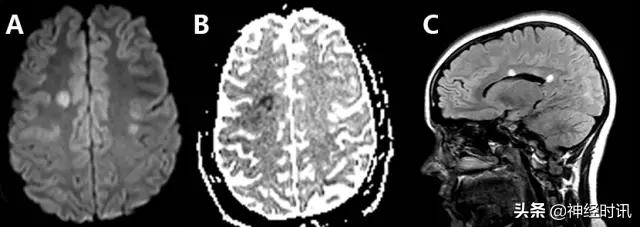

癫 痫

三分之一的卒中类似疾病是由于癫痫发作或发作后功能障碍导致。有时癫痫也可导致弥散受限(图2)。其分布特点不符合血管分布,水肿和脑回增强出现更早,脑灌注正常或增加,无血管闭塞,有时同时有皮层弥散受限和皮层下弥散增加。

图2 一例66岁男性,癫痫发作伴意识状态改变、急性失语和右侧凝视,拟诊脑卒中并给予IV-tPA治疗。左侧病灶情况下的右侧凝视可提示癫痫发作。他的入院MRI显示左侧额顶叶皮层和皮层下白质弥散受限(A和B)和水肿(C)。他的症状和影像学(图像未提供)显示在出院前完全缓解。